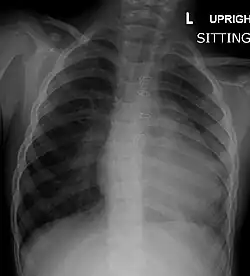

Chest radiograph

Before more sophisticated techniques became available, chest X-ray was the definitive method of diagnosis. The abnormal "coeur-en-sabot" (boot-like) appearance of a heart with tetralogy of Fallot is classically visible via chest X-ray, although most infants with tetralogy may not show this finding.[50] The boot like shape is due to the right ventricular hypertrophy present in TOF. Lung fields are often dark (absence of interstitial lung markings) due to decreased pulmonary blood flow.[51]: 171–172

| Right ventricular hypertrophy | The right ventricle is more muscular than normal, causing a characteristic boot-shaped (coeur-en-sabot) appearance as seen by chest X-ray. Due to the misarrangement of the external ventricular septum, the right ventricular wall increases in size to deal with the increased obstruction to the right outflow tract. This feature is now generally agreed to be a secondary anomaly, as the level of hypertrophy tends to increase with age.[45] |